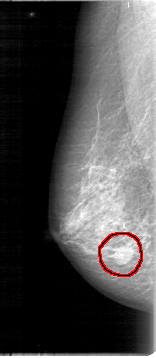

D_4012_1.RIGHT_MLO

RIGHT_MLO LINES 5356 PIXELS_PER_LINE 2326 BITS_PER_PIXEL 12 RESOLUTION 43.5 OVERLAY

FILE: D_4012_1.RIGHT_MLO.OVERLAY

TOTAL_ABNORMALITIES 1

ABNORMALITY 1

LESION_TYPE MASS SHAPE OVAL MARGINS OBSCURED

ASSESSMENT 0

SUBTLETY 5

PATHOLOGY BENIGN

TOTAL_OUTLINES 1

BOUNDARY